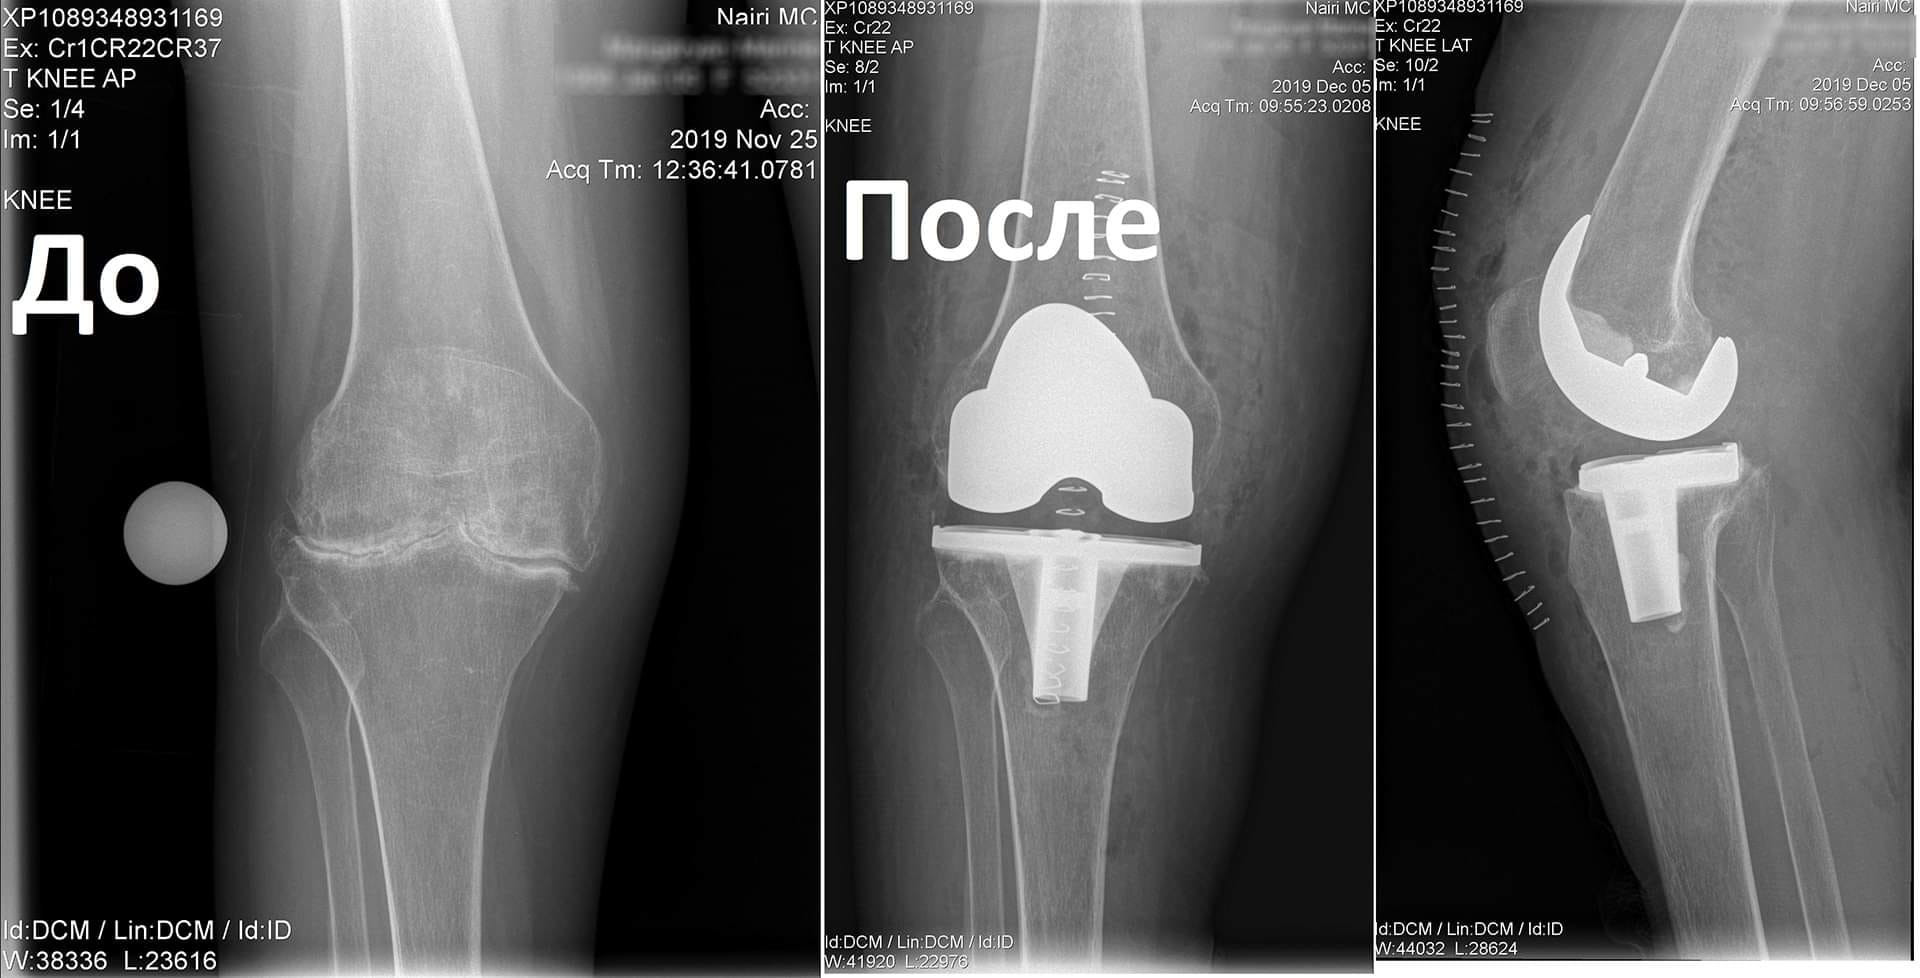

Կլինիկական դեպք. երկկողմանի գոնարթրոզ՝ ծնկահոդերի արթրոզ

Պացիենտը դիմել էր «Նաիրի» բժշկական կենտրոն` նստասալյակի օգնությամբ, ծանրագույն ցավերով, շարժումների խիստ սահմանափակումով:

Ծանրագույն պոլիարթրիտի հետևանքով առաջացել էր ծնկահոդերի արթրոզ։

Նախավիրահատական ընթացակարգից հետո իրականացվել է զույգ ծնկահոդերի փուլային էնդոպրոթեզավորում: Վիրահատությունից մի քանի ամիս անց պացիենտը չի ունեցել ցավեր, ազատ քայլել է և սկսել է ապրել լիարժեք կյանքով: